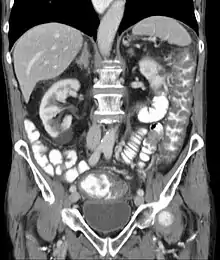

Prior to the advent of tests to detect C. difficile toxins, the diagnosis most often was made by colonoscopy or sigmoidoscopy. The appearance of "pseudomembranes" on the mucosa of the colon or rectum is highly suggestive, but not diagnostic of the condition.[42] The pseudomembranes are composed of an exudate made of inflammatory debris, white blood cells. Although colonoscopy and sigmoidoscopy are still employed, now stool testing for the presence of C. difficile toxins is frequently the first-line diagnostic approach. Usually, only two toxins are tested for—toxin A and toxin B—but the organism produces several others. This test is not 100% accurate, with a considerable false-negative rate even with repeat testing.[43]